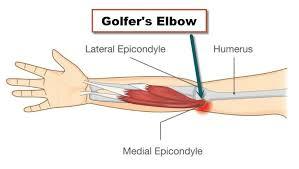

Golfer’s elbow, also called medial epicondylitis, is a painful condition occurring from repeated muscle contractions in the forearm that leads to inflammation and microtears in the tendons that attach to the medial epicondyle.

Golfer’s elbow and tennis elbow are similar, except that golfer’s elbow occurs on the inside of the elbow and tennis elbow occurs on the outside of the elbow. Both conditions are a type of tendonitis - inflammation of the tendons.

Golfer’s elbow is usually caused by the overuse of the forearm muscles and tendons that control wrist and finger movement, but may also be caused by direct trauma such as a fall, car accident or work injury.